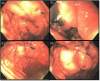

We report the first pediatric use of a laparoscopic-assisted endoscopic overstitch technique for managing an acutely perforated gastric ulcer in a 16-year-old female. The patient presented with symptoms consistent with gastrointestinal perforation, confirmed by radiologic pneumoperitoneum. Diagnostic laparoscopy identified inflammatory adhesions and a gastric ulcer perforation. Concurrent endoscopy precisely located the defect, which was effectively closed using an endoscopic overstitch device mounted on a therapeutic double-channel gastroscope. Closure involved three full-thickness inverted figure-of-eight sutures, verified by an intraoperative leak test and reinforced with an omental patch. Postoperative recovery was rapid and uncomplicated, progressing to a regular diet within 3 days. This innovative hybrid laparoscopic-endoscopic technique demonstrates efficacy, safety, and the benefits of minimally invasive surgery for pediatric gastrointestinal perforations, emphasizing its potential superiority over traditional methods.